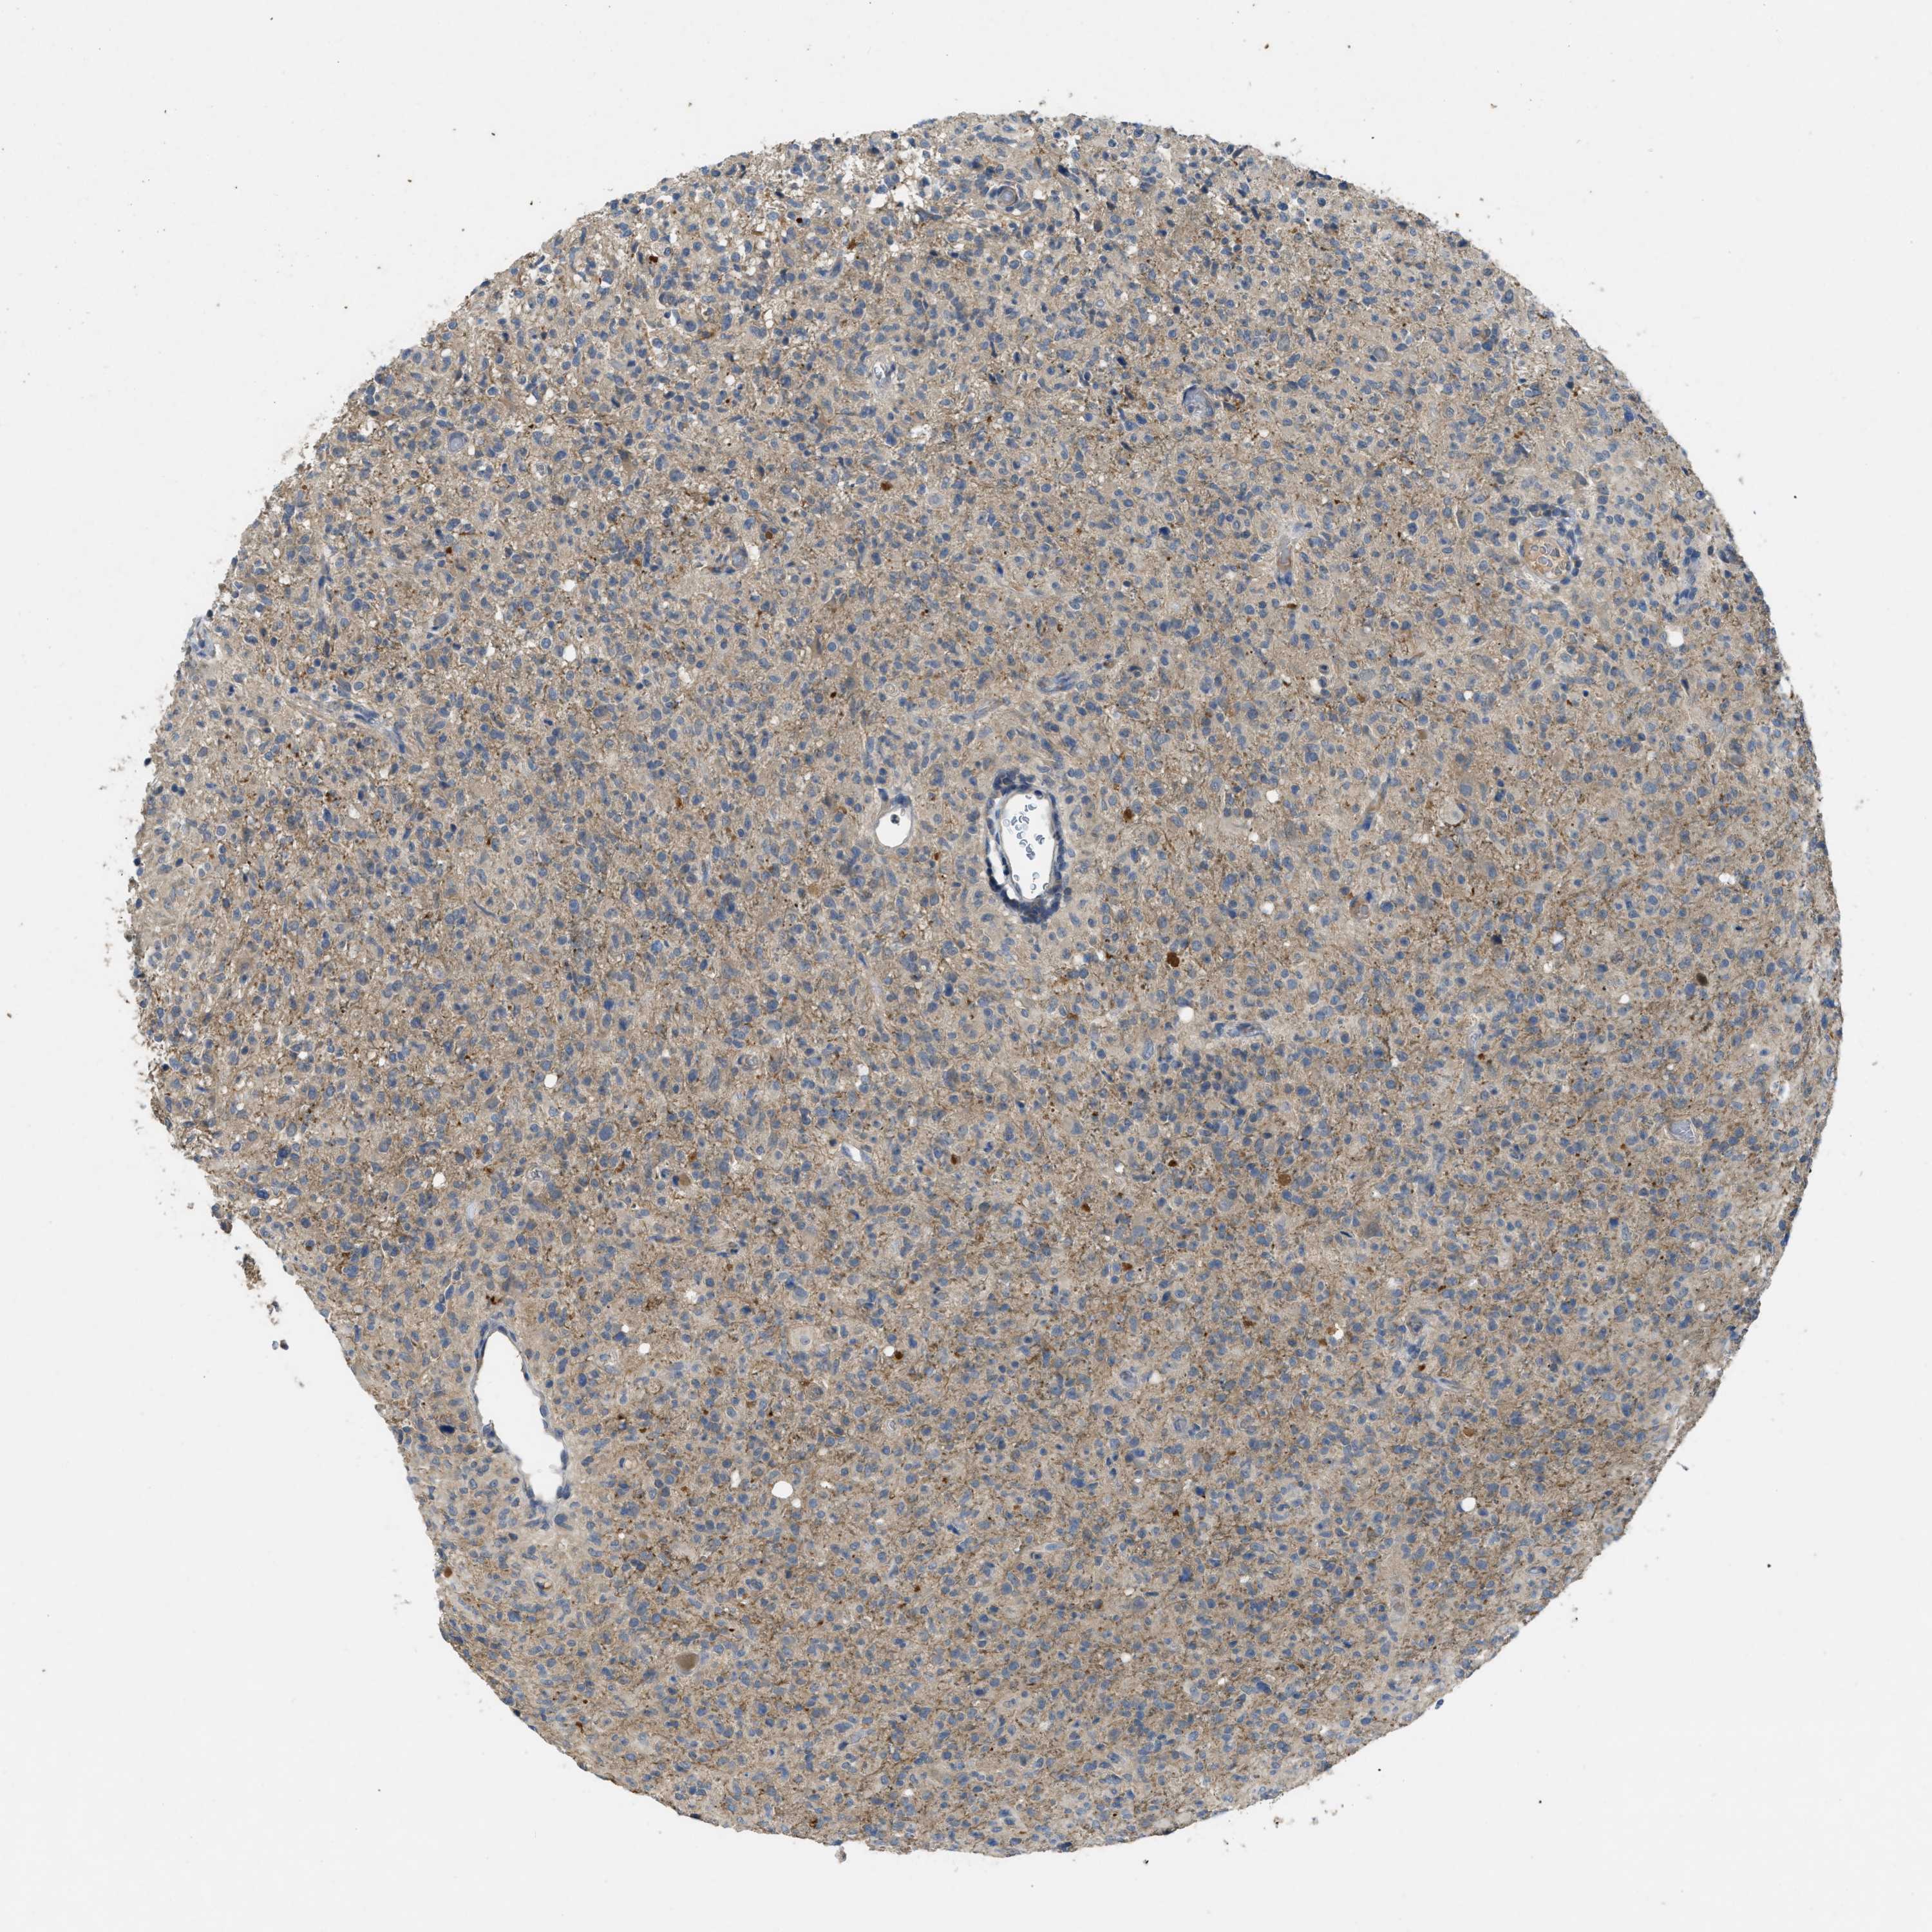

GLIOMA - Protein expressioni

A mouse-over function shows sample information and annotation data. Click on an image to view it in a full screen mode. Samples can be filtered based on level of antibody staining by selecting one or several of the following categories: high, medium, low and not detected. The assay and annotation is described here.

Note that samples used for immunohistochemistry by the Human Protein Atlas do not correspond to samples in the TCGA dataset.

Antibody stainingi

Antibody staining in the annotated cell types in the current human tissue is reported as not detected, low, medium, or high, based on conventional immunohistochemistry profiling in selected tissues. This score is based on the combination of the staining intensity and fraction of stained cells.

Each image is clickable and will lead to virtual microscopy that enables deeper exploration of all samples and also displays staining intensity scores, fraction scores and subcellular localization as well as patient and tissue information for each sample.

Antibody HPA012778

Antibody CAB018581

Staining

High

Medium

Low

Not detected

Intensity

Strong

Moderate

Weak

Negative

Quantity

>75%

75%-25%

<25%

None

Location

Nuclear

Cytoplasmic/membranous

Cytoplasmic/membranous,nuclear

Glioma, malignant, High grade

Glioma, malignant, Low grade